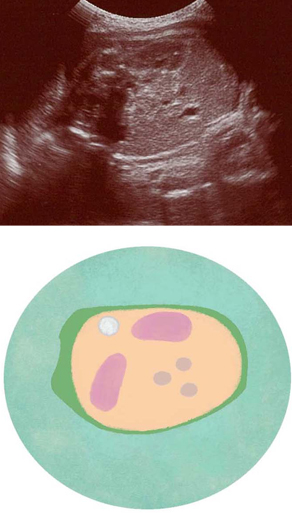

妊娠34週ころの超音波写真

腎臓などの内臓が鮮明に見えてきます

内臓のつくりがよく見えるようになります。2つの黒いだ円が腎臓。赤ちゃんが飲み込んだ羊水は、腎臓でろ過され、おしっことして羊水中に出されます。